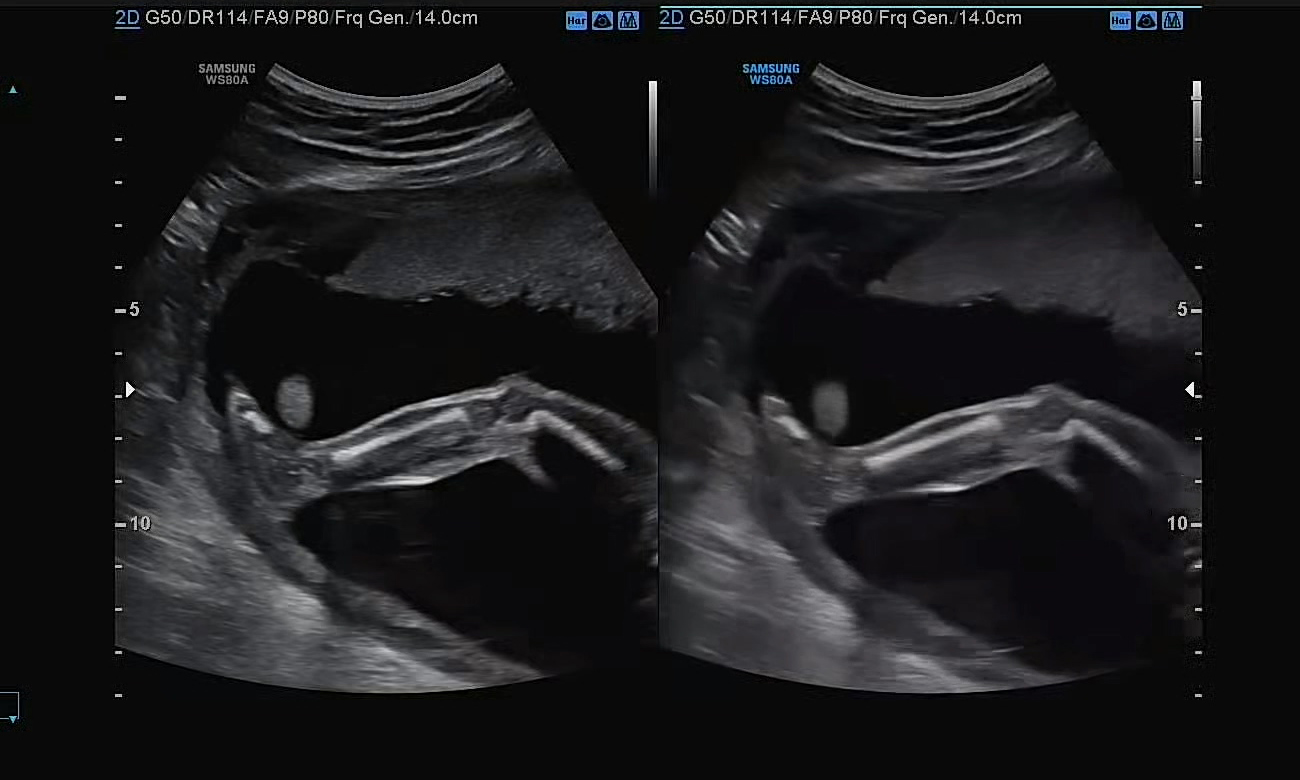

발가락도 힘겹게 여기저기 둘러보며 캡쳐한 모습! 다행히 왼발, 오른발 발가락이 무사히 형성된 모습이다.